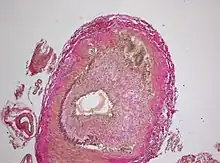

The gold standard for diagnosing temporal arteritis is biopsy, which involves removing a small part of the vessel under local anesthesia and examining it microscopically for giant cells infiltrating the tissue.[19] However, a negative result does not definitively rule out the diagnosis; since the blood vessels are involved in a patchy pattern, there may be unaffected areas on the vessel and the biopsy might have been taken from these parts. Unilateral biopsy of a 1.5–3 cm length is 85-90% sensitive (1 cm is the minimum).[20] A characterised as intimal hyperplasia and medial granulomatous inflammation with elastic lamina fragmentation with a CD 4+ predominant T cell infiltrate, currently biopsy is only considered confirmatory for the clinical diagnosis, or one of the diagnostic criteria.